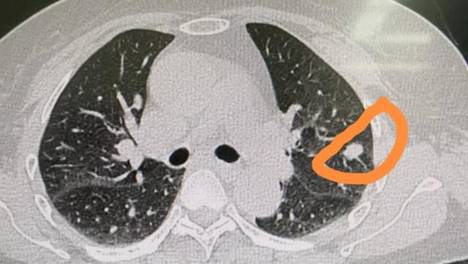

肺癌一查就是晚期?出现5种症状要当心!

约有25%至40%的肺癌患者会出现咳血症状,这是肺癌的一个重要警示信号。此外,若肿瘤侵犯周围组织或发生转移,还可能出现声音嘶哑、吞咽困难等症状。需要注意的是,这些症状也可能由其他疾病引起,因此出现症状时不必过…